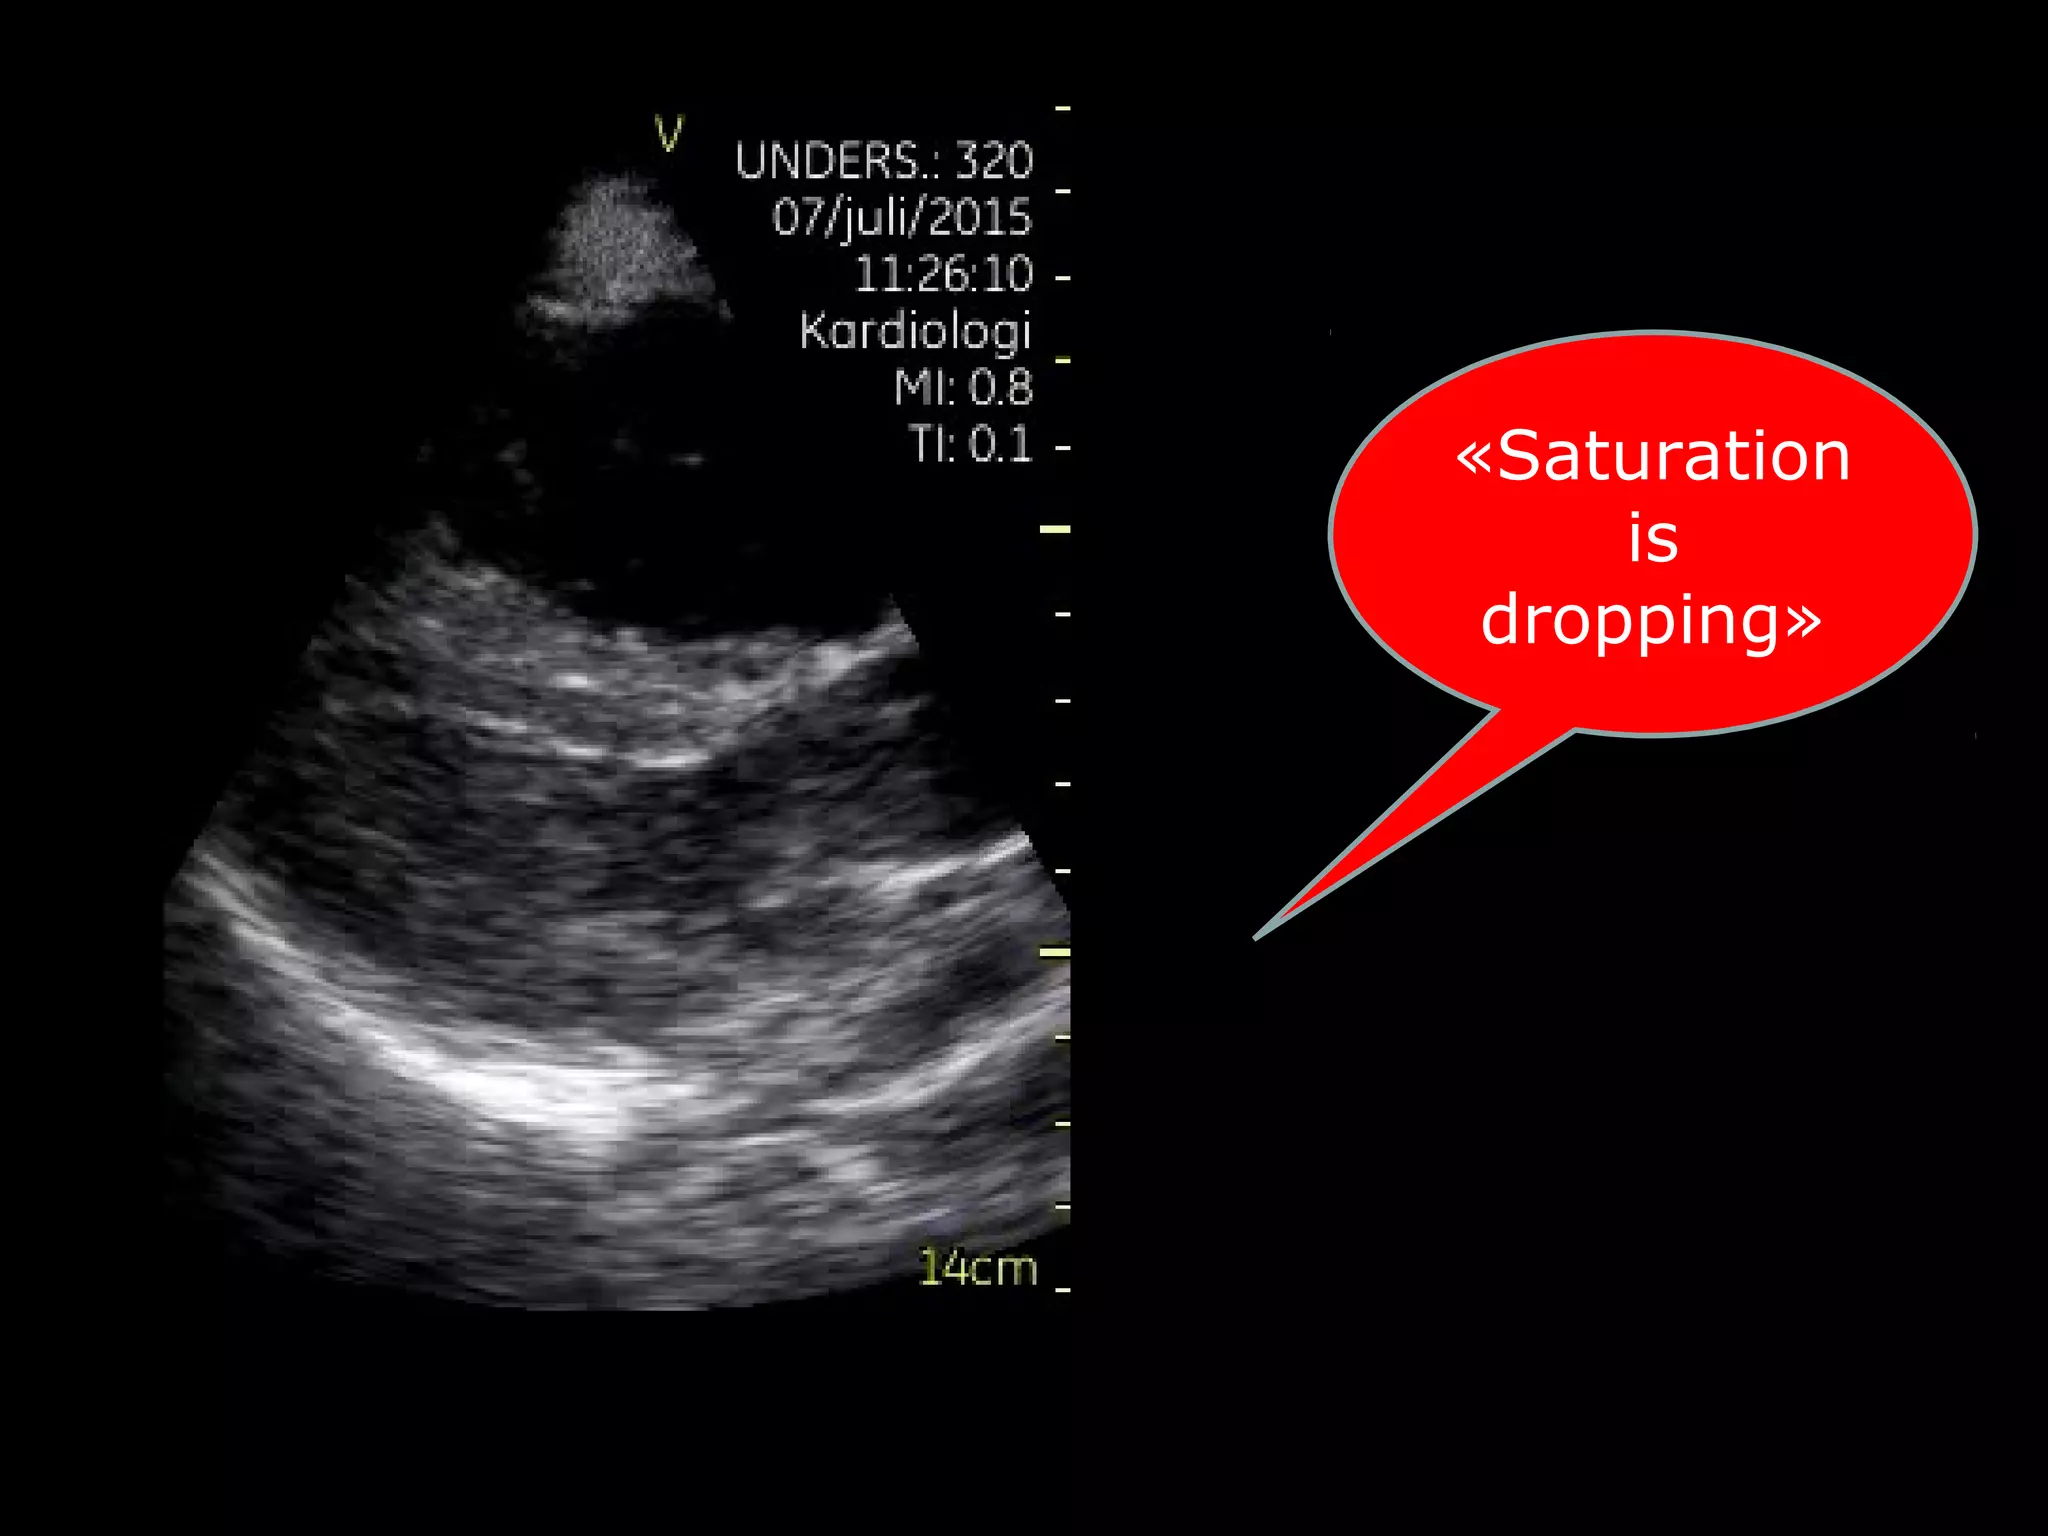

«Saturation

is

dropping»